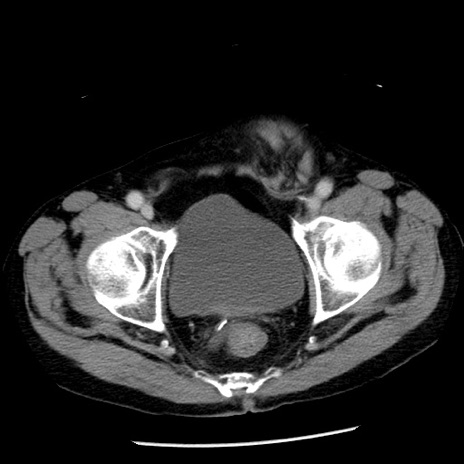

症例26(横断像)

【症例】80歳代男性

【主訴】嘔吐

【現病歴】昨晩2回嘔吐あり、今朝になっても嘔吐あり。来院。

【既往歴】胃潰瘍

【身体所見】意識清明、BT 37.6℃、BP 166/95mmHg、HR 100bpm、SpO2 97%、腹部:平坦・軟、腸蠕動音聴取良好、圧痛なし。

【データ】WBC 21900、CRP 1.46